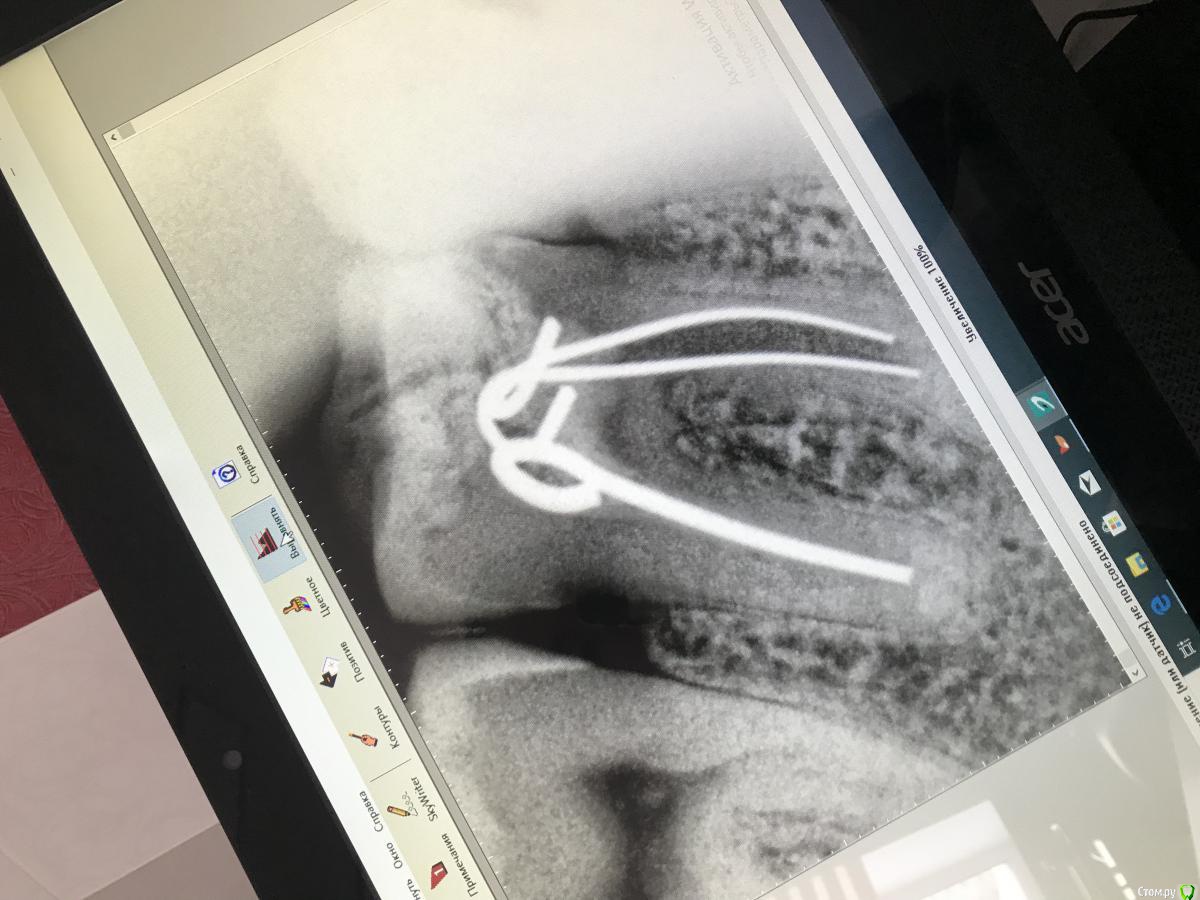

Mashaa1337 Опубликовано 15 января, 2020 Автор Поделиться Опубликовано 15 января, 2020 Здравствуйте . Пациентка жалуется только на скол пломбы , никаких жалоб больше нет , зуб лечили более 10 лет назад в государственной поликлинике. Я не понимаю , чем запломбированы каналы , после препарирования увидела данный материал , он похож на какие-то металлические ленточки, гибкие. Может вы знаете , что это? Ссылка на комментарий

vse32 Опубликовано 15 января, 2020 Поделиться Опубликовано 15 января, 2020 Так это штифты серебряные, вероятно. 3 Ссылка на комментарий